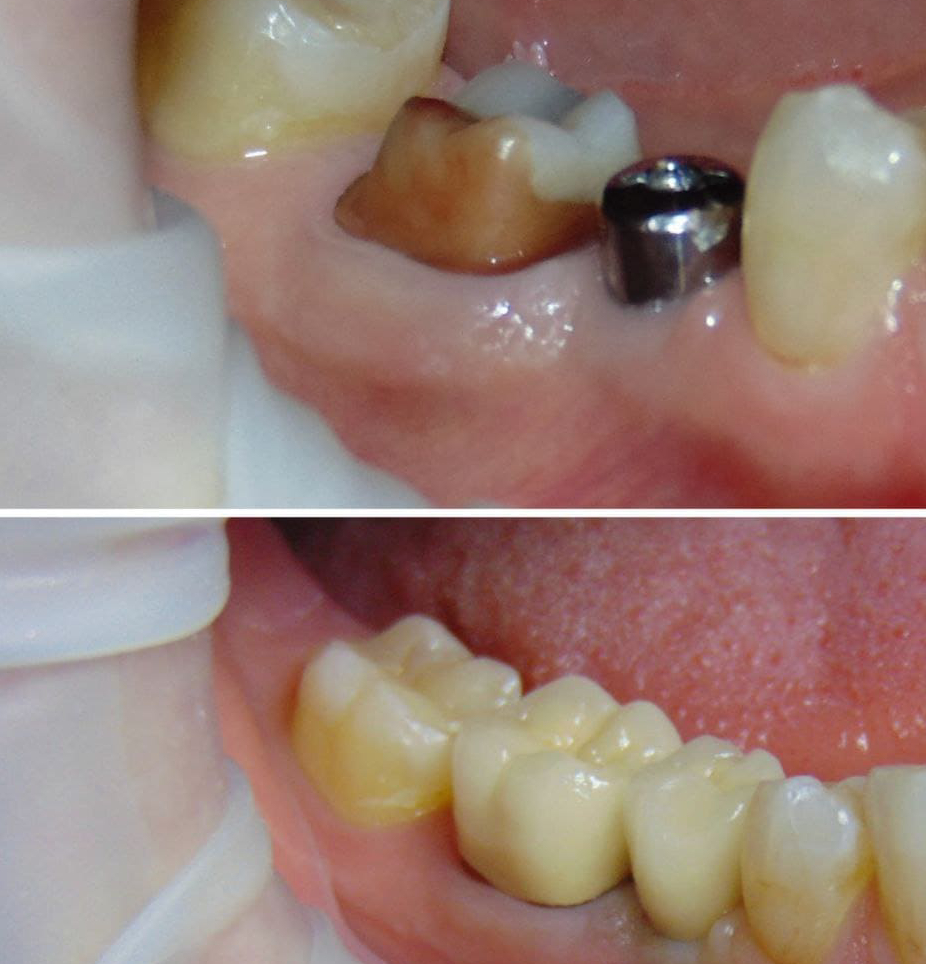

Установка двух имплантов и двух коронок

Цель визита пациента

- Пациентка Марина обратилась в нашу клинику с жалобами на отсутствие зубов в области 35, 46 зз

Детали лечебного процесса

- После КТ исследования были установлены 2 имплантата. С последующей установкой керамических коронок

Продолжительность и этапы лечения

- 2 месяца

- 3 визита